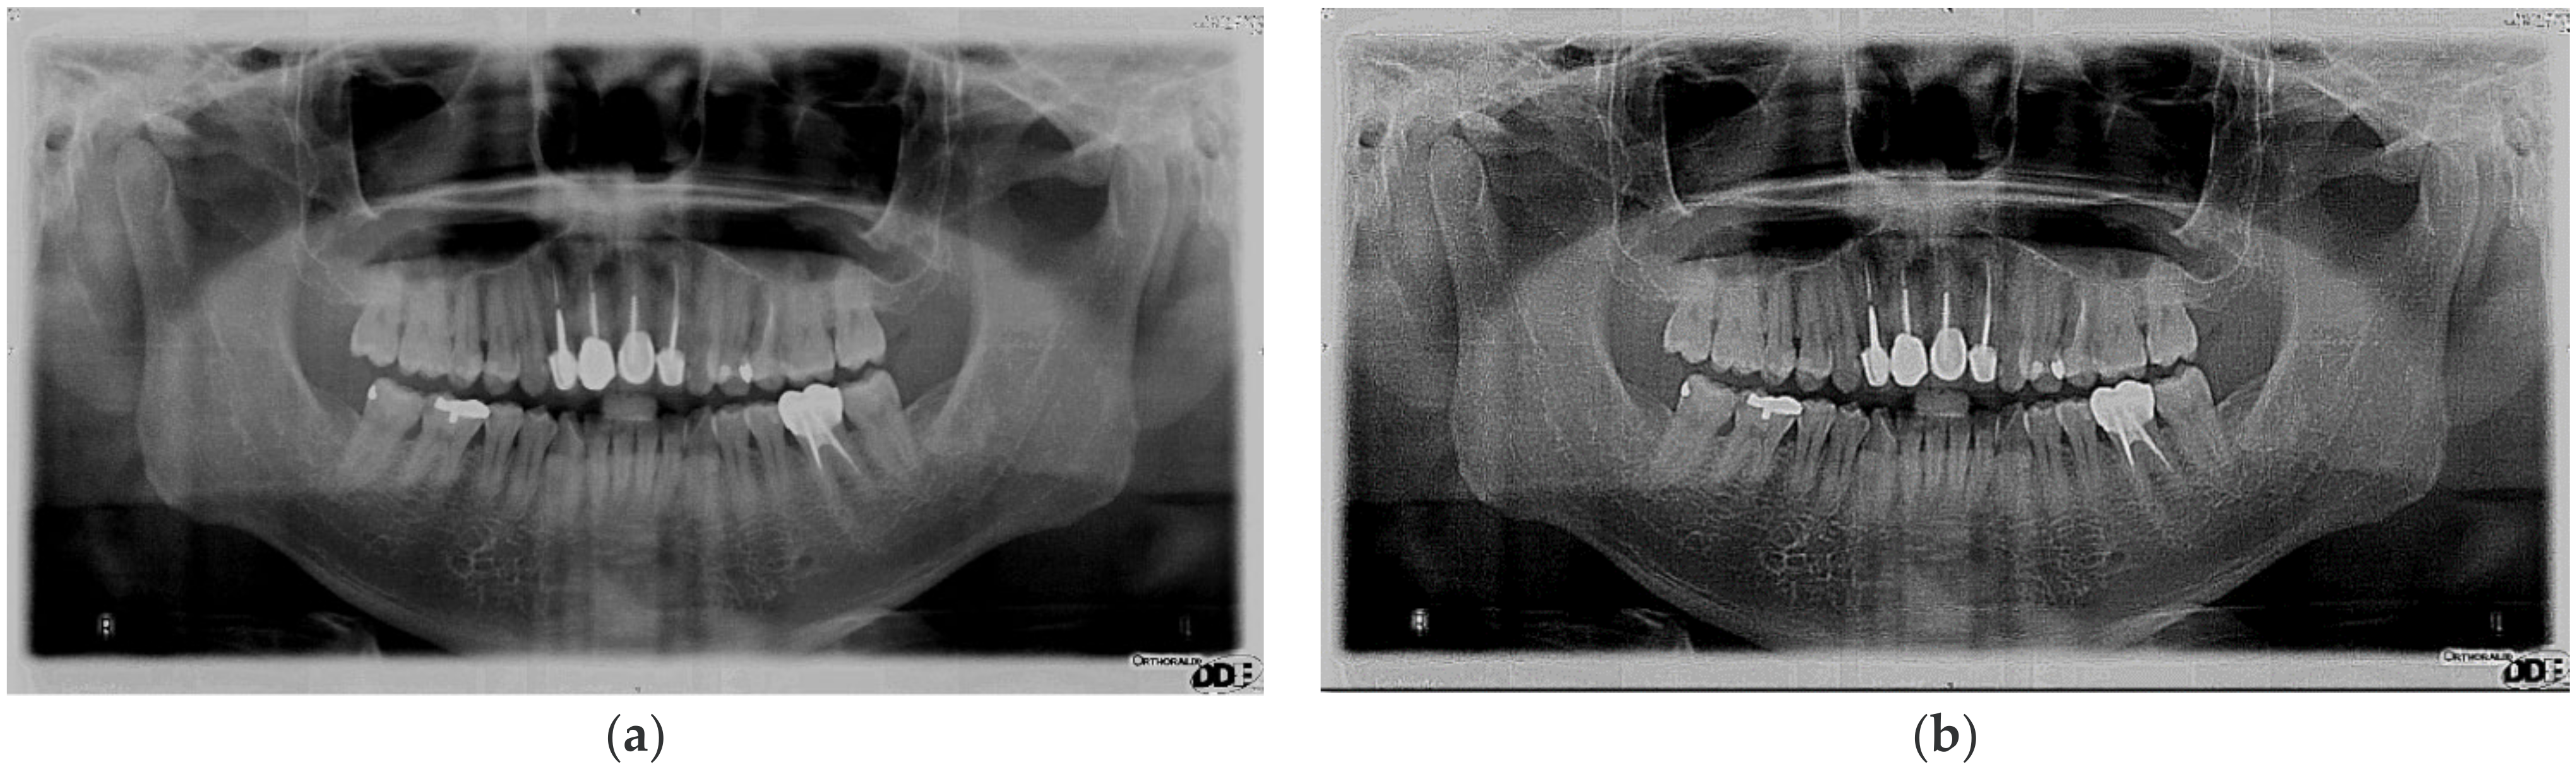

2.1.1. Sharpening

2.1.2. Image Contrast Adjustment

2.1.3. Flat-Field Correction

2.1.4. Adaptive Histogram Equalization

| Image Enhancement in Cutting Accuracy Rate | |||||

| Original Image | Matrix Operation Diagram | Image Contrast Adjustment | Flat-Field Correction | Adaptive Histogram Equalization | |

| Cutting accuracy rate | 34.72% | 51.68% | 58.74% | 78.61% | 89.95% |